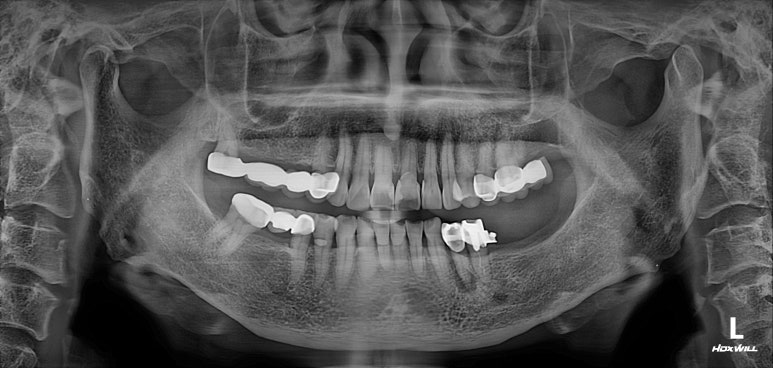

저희 병원에 작년에 오셨던 여자환자분입니다.

왼쪽 아래 어금니가 2개가 없으신 것을 아실 수 있으실텐데,

그 자리에 편측 틀니를 쓰고 계셨고, 너무너무 불편하여 임플란트로 치료 받으러 내원하셨습니다.

왼쪽 아래 큰어금니 두개가 없었고,

교합면 사진을 보시면, 앞의 두 치아에 surveyed crown (서베이드 크라운)을 설치하고 부분 틀니를 사용하게 하심을 단번에 알 수 있었습니다.

중요한 것은 해당 부위의 대구치 두 개를 뽑은지가 너무 오래되셨고, 틀니를 사용하셔서

대부분의 부착치은 (각화치은)이 사라져 있는 상태였습니다.

그래서 유리치은 이식술을 강하게 권유드렸고, 환자분이 다행히도 필요성을 이해해주셨어요.

마무리는 갈끔한 엑스레이 사진으로 !!!